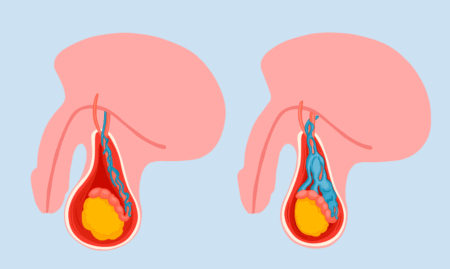

دوالي الخصية

- تعني الدوالي الخصية استئصال الأوردة المتوسعة داخل كيس الصفن، والمعروفة بالدوالي.

- الدوالي أكثر شيوعًا في الجانب الأيسر من الخصية، وعادةً لا تظهر عليها أعراض، لكنها قد تسبب أحيانًا ألمًا يتراوح بين ألم حاد ومفاجئ إلى شعور بعدم الراحة الخفيف في منطقة الخصيتين، ويزداد سوءًا عند الوقوف أو ممارسة النشاط البدني، وعادةً يزداد خلال النهار ويخف عند الاستلقاء.

- قد تحدث نتيجة اضطراب في تدفق الدم في الأوردة التي تصل الدم إلى الخصيتين أو تصرفه منه.

- كما يمكن أن تحدث نتيجة خلل في وظيفة الأوردة الخصوية.